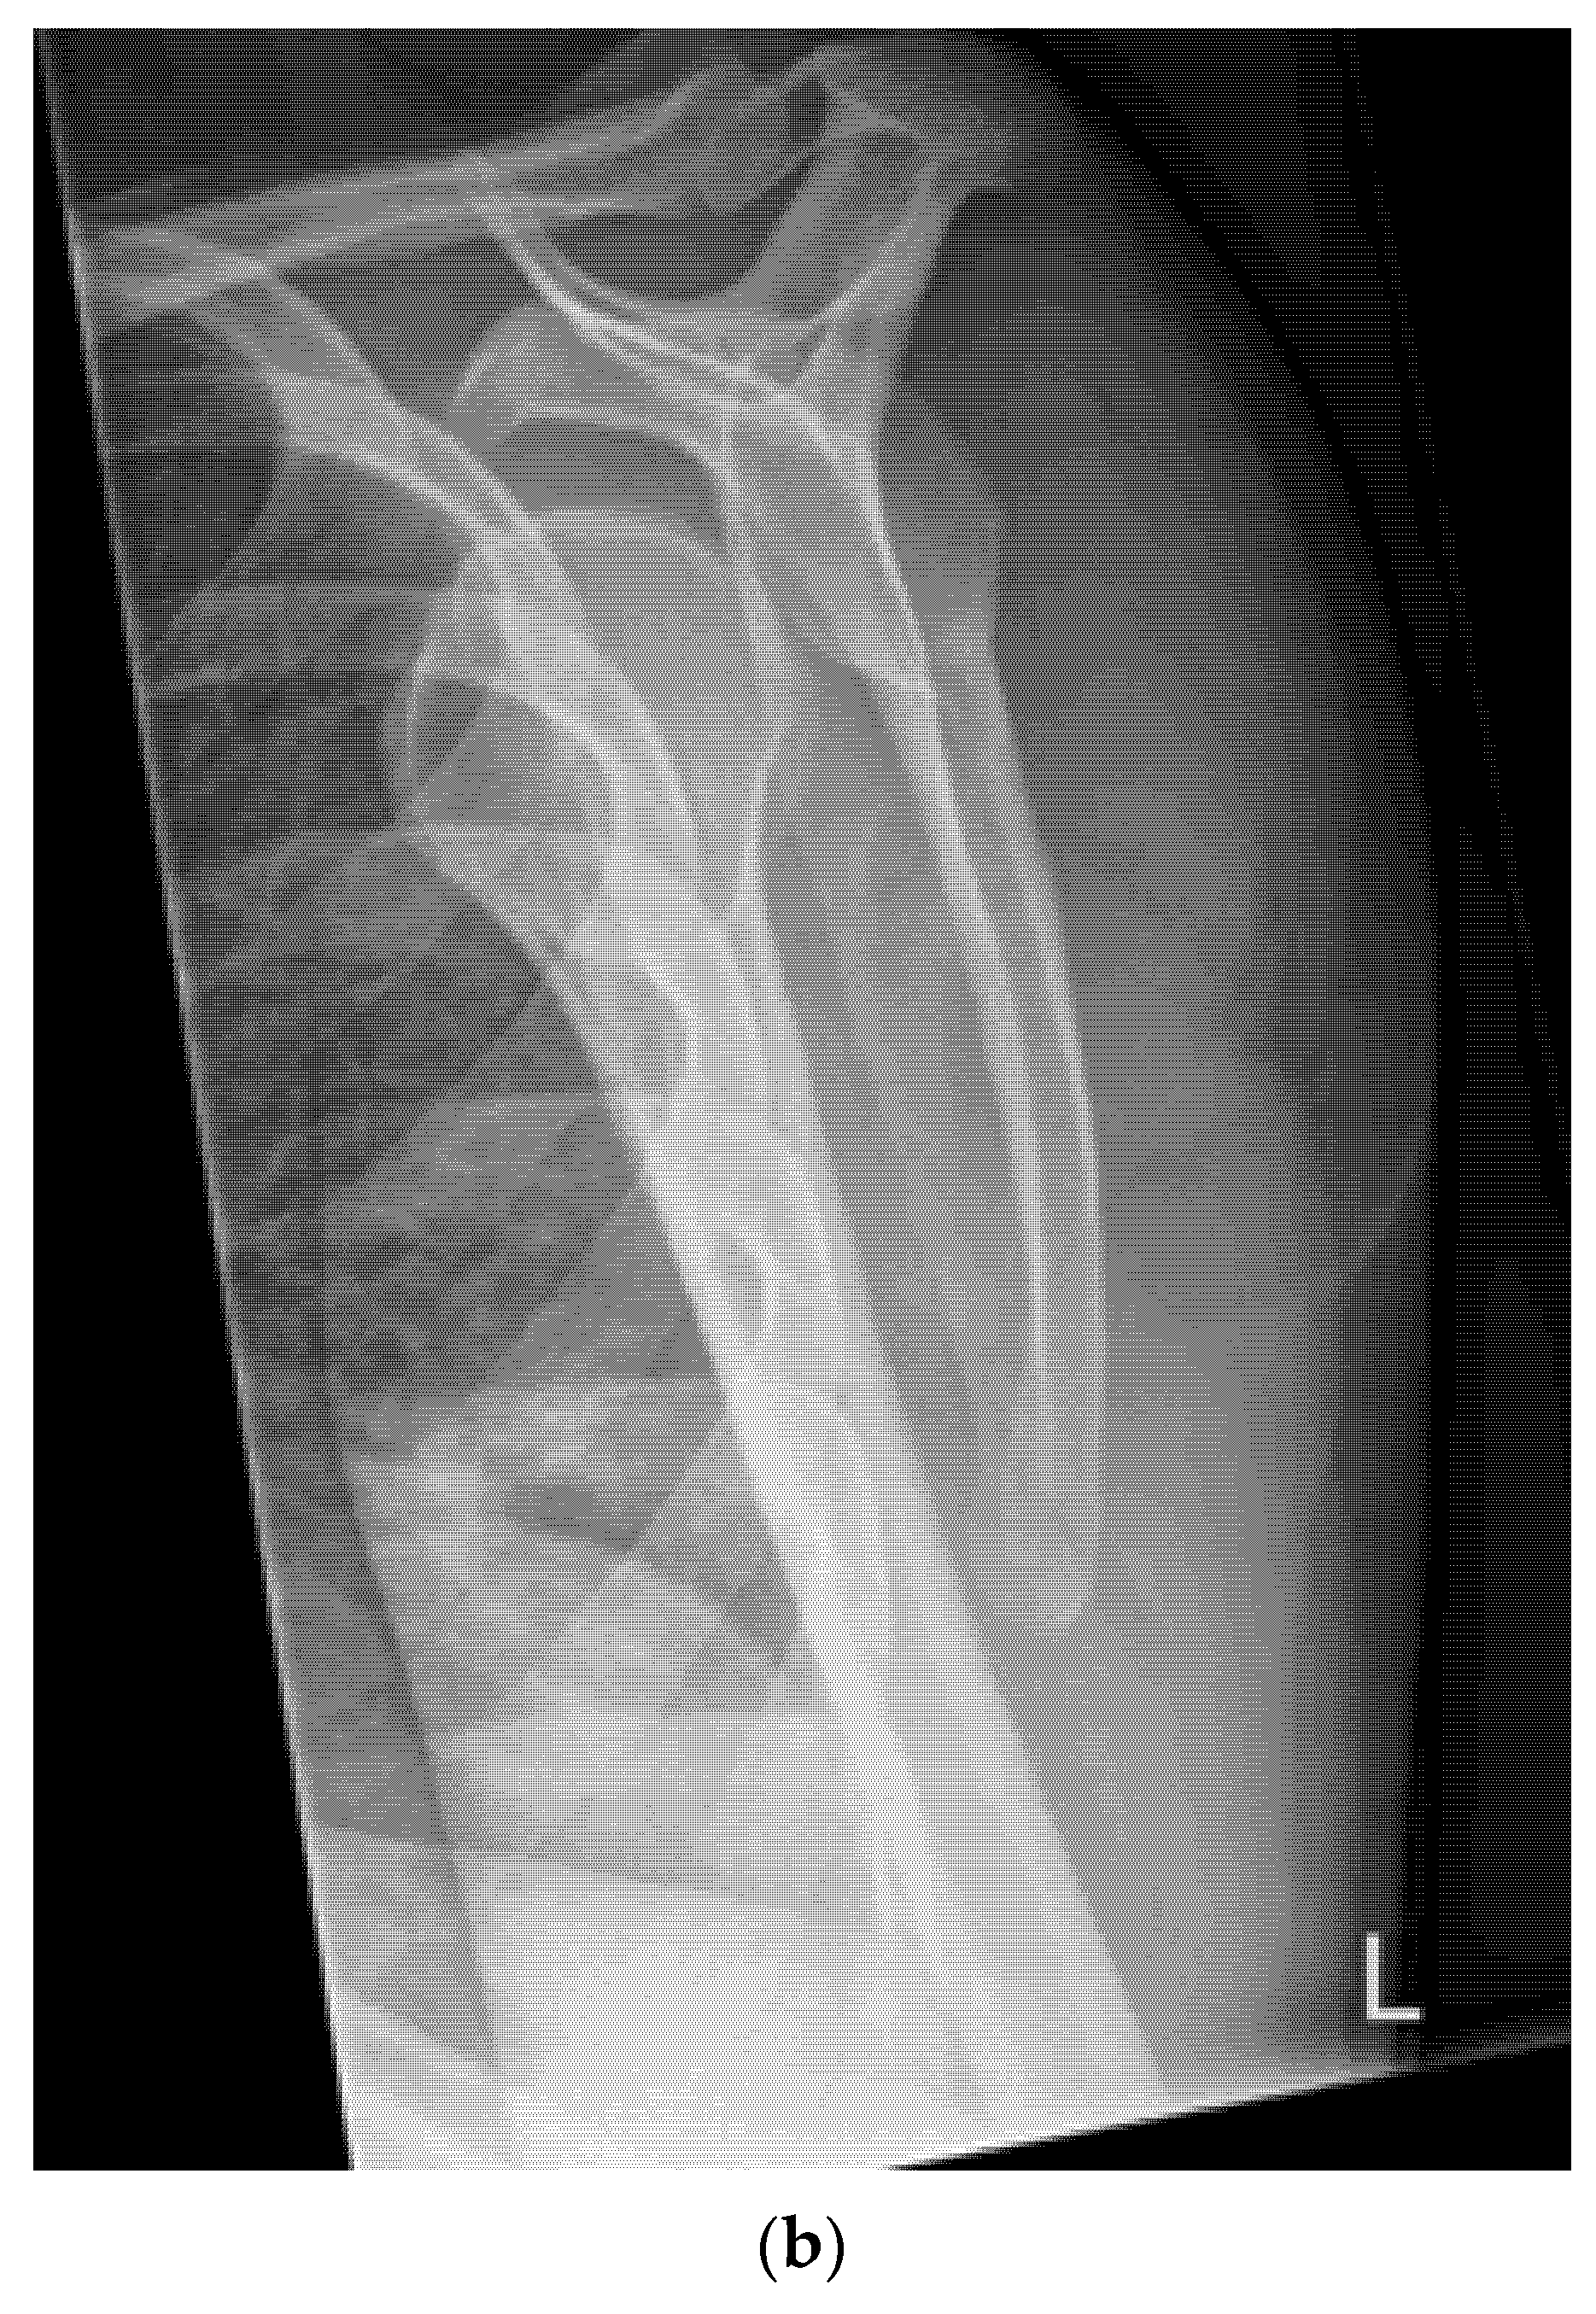

- Quick exclusion of fractures in shoulder dislocations for timely reduction (Figure 13).

- Recommendation 6: Ultrasound should be integrated into the assessment and management of shoulder injuries, including proximal humerus fractures, shoulder dislocations, and post-relocation maneuvers, both prehospitally, in emergency departments, and other acute care settings.

- Example: Suspected left shoulder dislocation